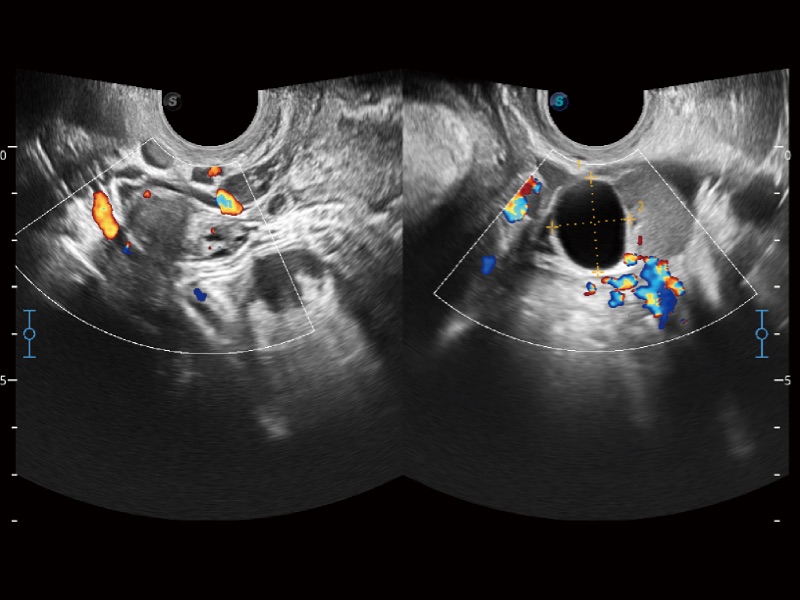

婦產(chǎn)科應(yīng)用

高分辨率血流成像技術(shù)提高了對(duì)低速血流信號(hào)的檢測(cè)能力。在提高空間分辨率的同時(shí),也克服了血流外溢現(xiàn)象,為用戶(hù)提供更加真實(shí)的血流動(dòng)力學(xué)信息。